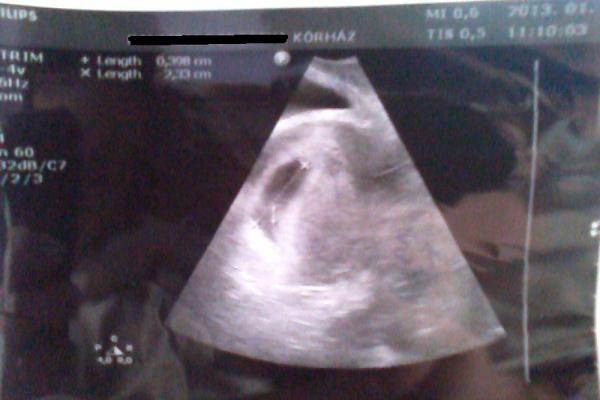

Hope gratula a kisbabához, nagyon nagy öröm egy ilyen felvétel már

!